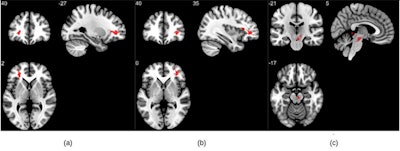

Group analysis on susceptibility-weighted imaging exhibiting higher susceptibility-weighted imaging values in the COVID group when compared to healthy controls. Three significant clusters were found primarily in the white matter regions of the prefrontal cortex and in the brainstem. The clusters (A) and (B) are observed bilaterally in the cerebral white matter near the orbitofrontal gyrus, whereas (C) lies in the midbrain region. Image and caption courtesy of the RSNA and Sapna Mishra.Different compounds in the body such as blood, iron, and calcium, carry different "magnetic susceptibility" on MRI, Mishra noted, and tracking these differences can help detect and monitor conditions such as microbleeds, vascular abnormalities, brain tumors, and stroke, the researchers explained.

The study showed that participants who had COVID-19 and recovered had higher susceptibility values on MRI in their frontal lobes and brain stems compared to the healthy controls -- brain regions linked to fatigue, insomnia, depression, headaches, and cognitive disruptions, according to Mishra's group. The researchers also found differences in the right ventral diencephalon area of the brain stem, which coordinates the endocrine system and regulates the sleep-wake cycle, among other tasks.